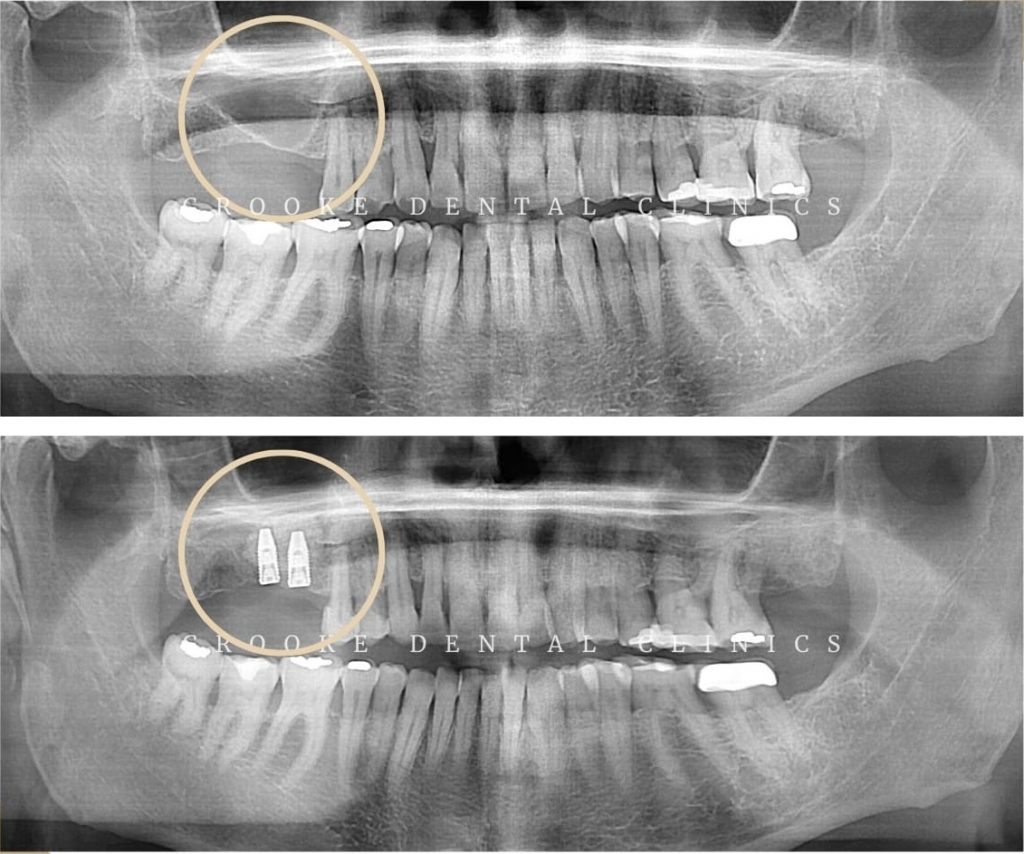

Elevación de seno maxilar – La solución para colocar implantes dentales con pérdida de hueso

Los implantes dentales se han convertido en el tratamiento más seguro y cómodo para solucionar problemas de pérdidas dentales. Una vez colocado, el implante se